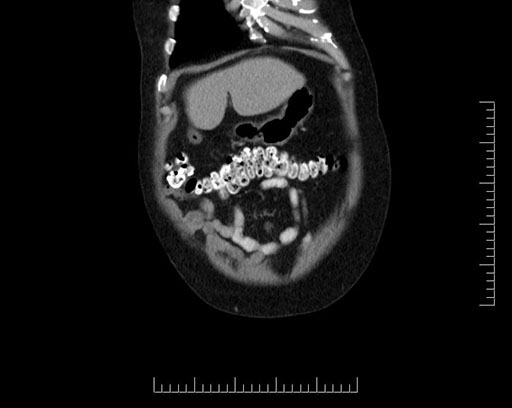

Coronal - stented